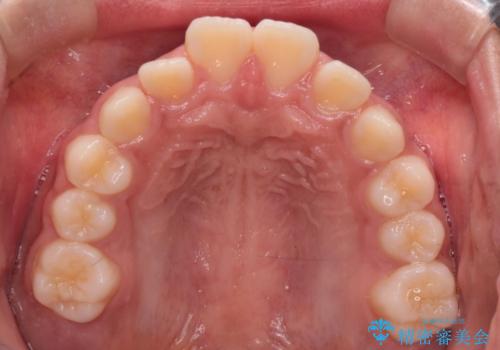

- 患者様は前歯の突出を主訴に来院されました。診査の結果、上顎の前歯が前方に傾斜しており、口元がやや突出して見える状態でした。一般的にこのようなケースでは抜歯矯正が選択肢となりますが、**患者様が抜歯を希望されなかったため、非抜歯での遠心移動(奥へ動かす治療)を計画しました。そのため、リンガルアーチ(歯の裏側に装着する装置)とTAD(歯科矯正用アンカースクリュー)**を併用し、上顎の歯を後方へ移動させながら噛み合わせを整える方法を選択しました。